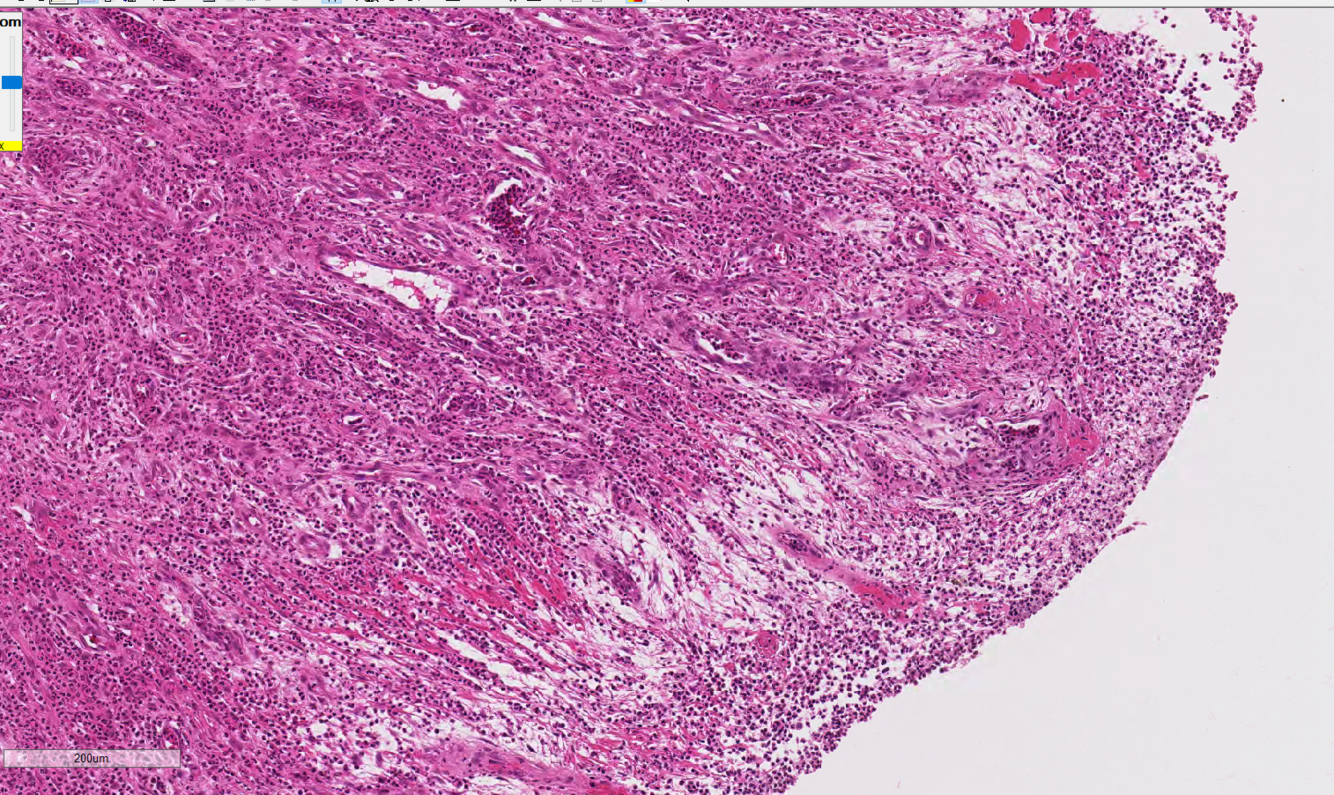

Histologic examination of the lesion shows that the mass is composed of spindles cells (mesenchymal cells) resembling osteoblasts that surround osteoid matrix. The spindle cells have a high mitotic rate are seen invading and replacing normal medulla and cortical bone. Provide a morphologic diagnosis based on this information.

proximal tibia: osteosarcoma, primary site